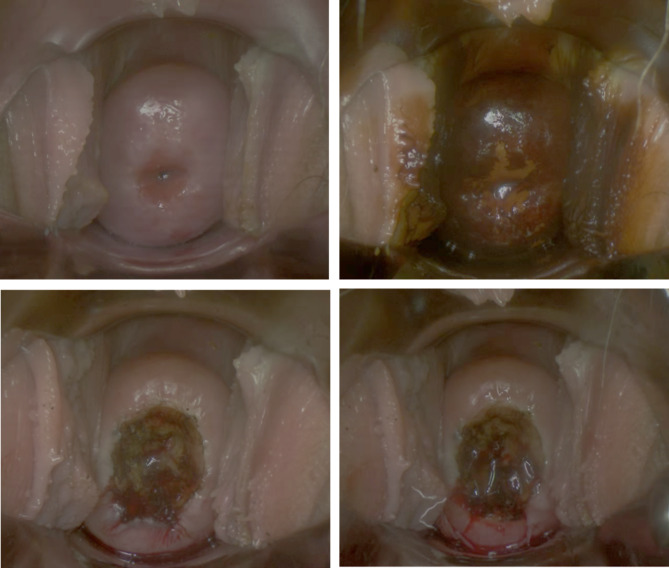

In the experimental group, a subset of patients received local application of recombinant human basic fibroblast growth factor (rbFGF) on the cervix after the use of the electrosurgical knife and before the placement of vaginal packing (Fig. 1).

Fig. 1.

LEEP procedure and rbFGF gel application